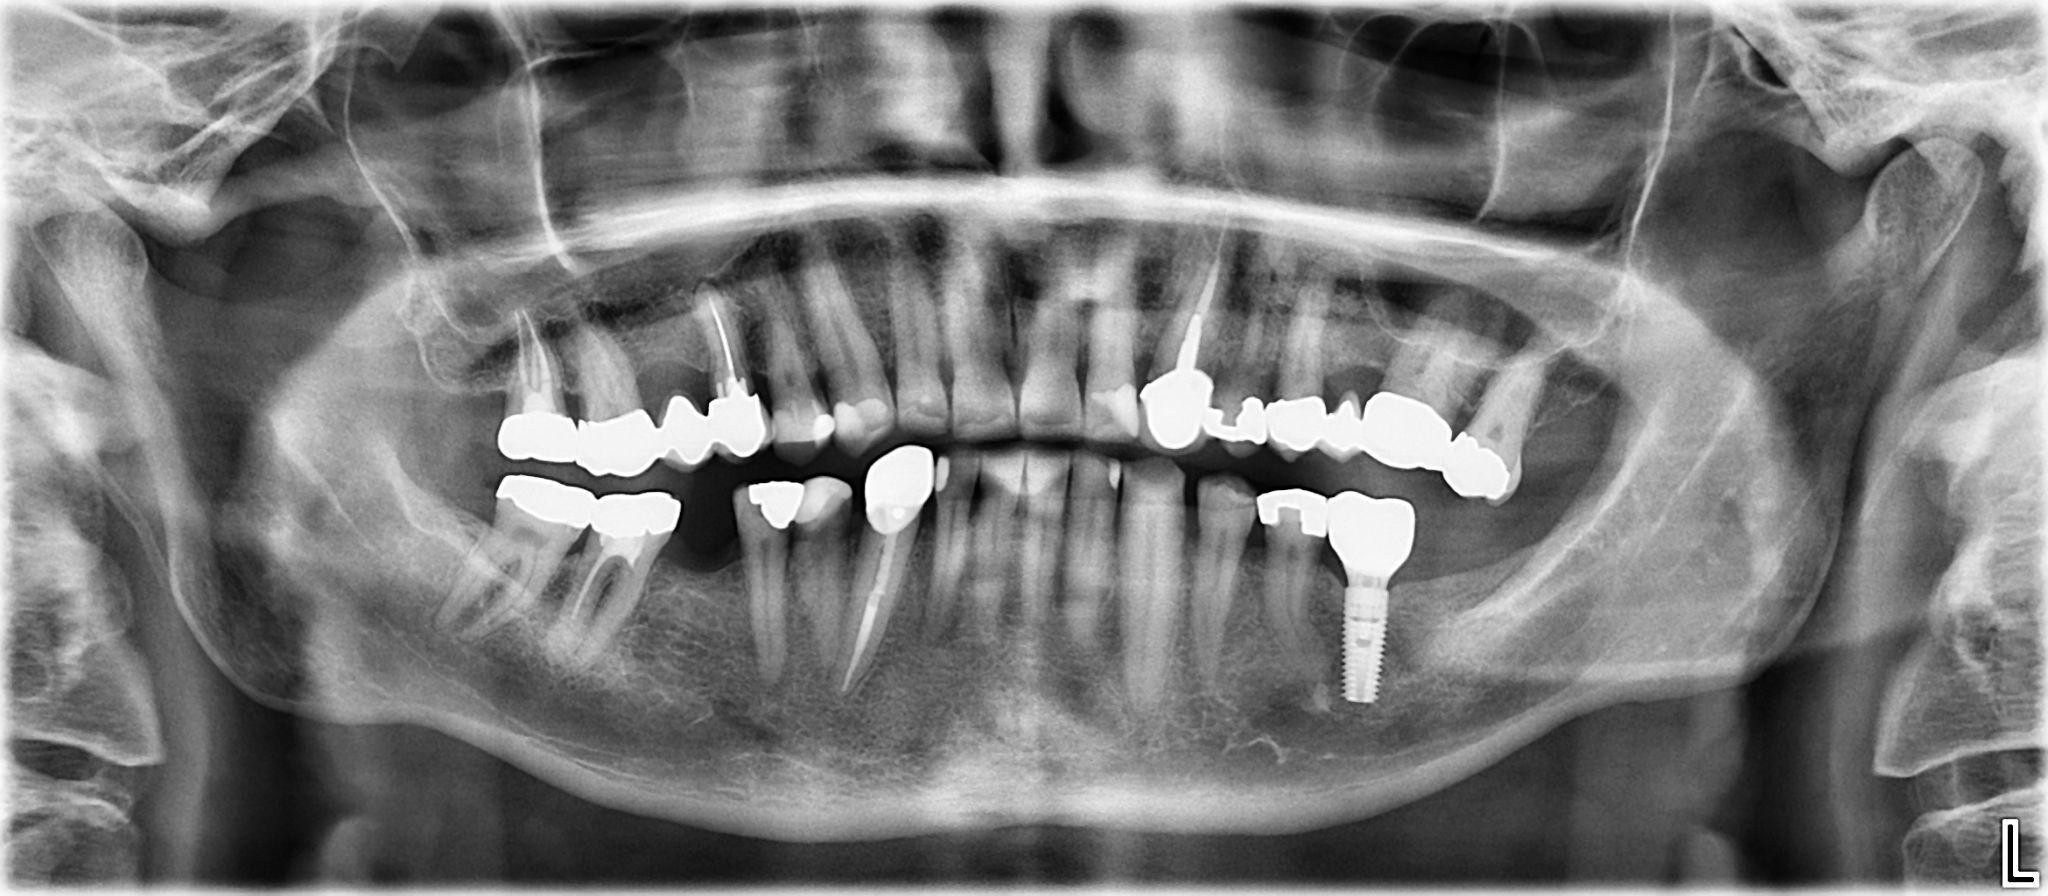

10. What option cannot be selected for the first quadrant of this panoramic X ray?

11. What option cannot be selected for the second quadrant of this panoramic X ray?

12. What option cannot be selected for the third quadrant of this panoramic X ray?

13. What option cannot be selected for the forth quadrant of this panoramic X ray?

14. What option cannot be selected for the upper jaw of this panoramic X ray?

15. What option cannot be selected for the lower jaw of this panoramic X ray?

16. What option cannot be selected for the upper jaw of this panoramic X ray?

17. What option cannot be selected for the lower jaw of this panoramic X ray?